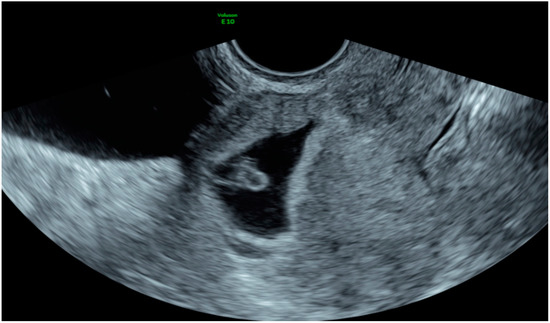

| Case 2 | Asymptomatic | 6 + 6 | 10,862 | GS 20 × 19 mm; with embryo | Hys: 1st step: CP resection by twizzle; IC Foley catheter 2nd step: vessels electrocoagulation by bipolar twizzle | Reoperation (hys) due to tissue residues and cervical laceration Complete resolution |

| Case 3 | Asymptomatic | 5 | 9747 | GS 20 × 22 mm; no embryo | MTX IM 50 mg/m2 of body surface + Hys | Complete resolution Currently pregnant (PMA Homologous) |

| Case 4 | Brownish vaginal discharge | 6 + 6 | 55,951 | GS 30 × 10 mm; no embryo | Hys | Complete resolution |

| Case 6 | Vaginal bleeding | 6 | 4274 | GS 5.4 × 5 mm with embryo | MTX IM 50 mg/m2 of body surface + Hys: CP resection by twizzle | Complete resolution |